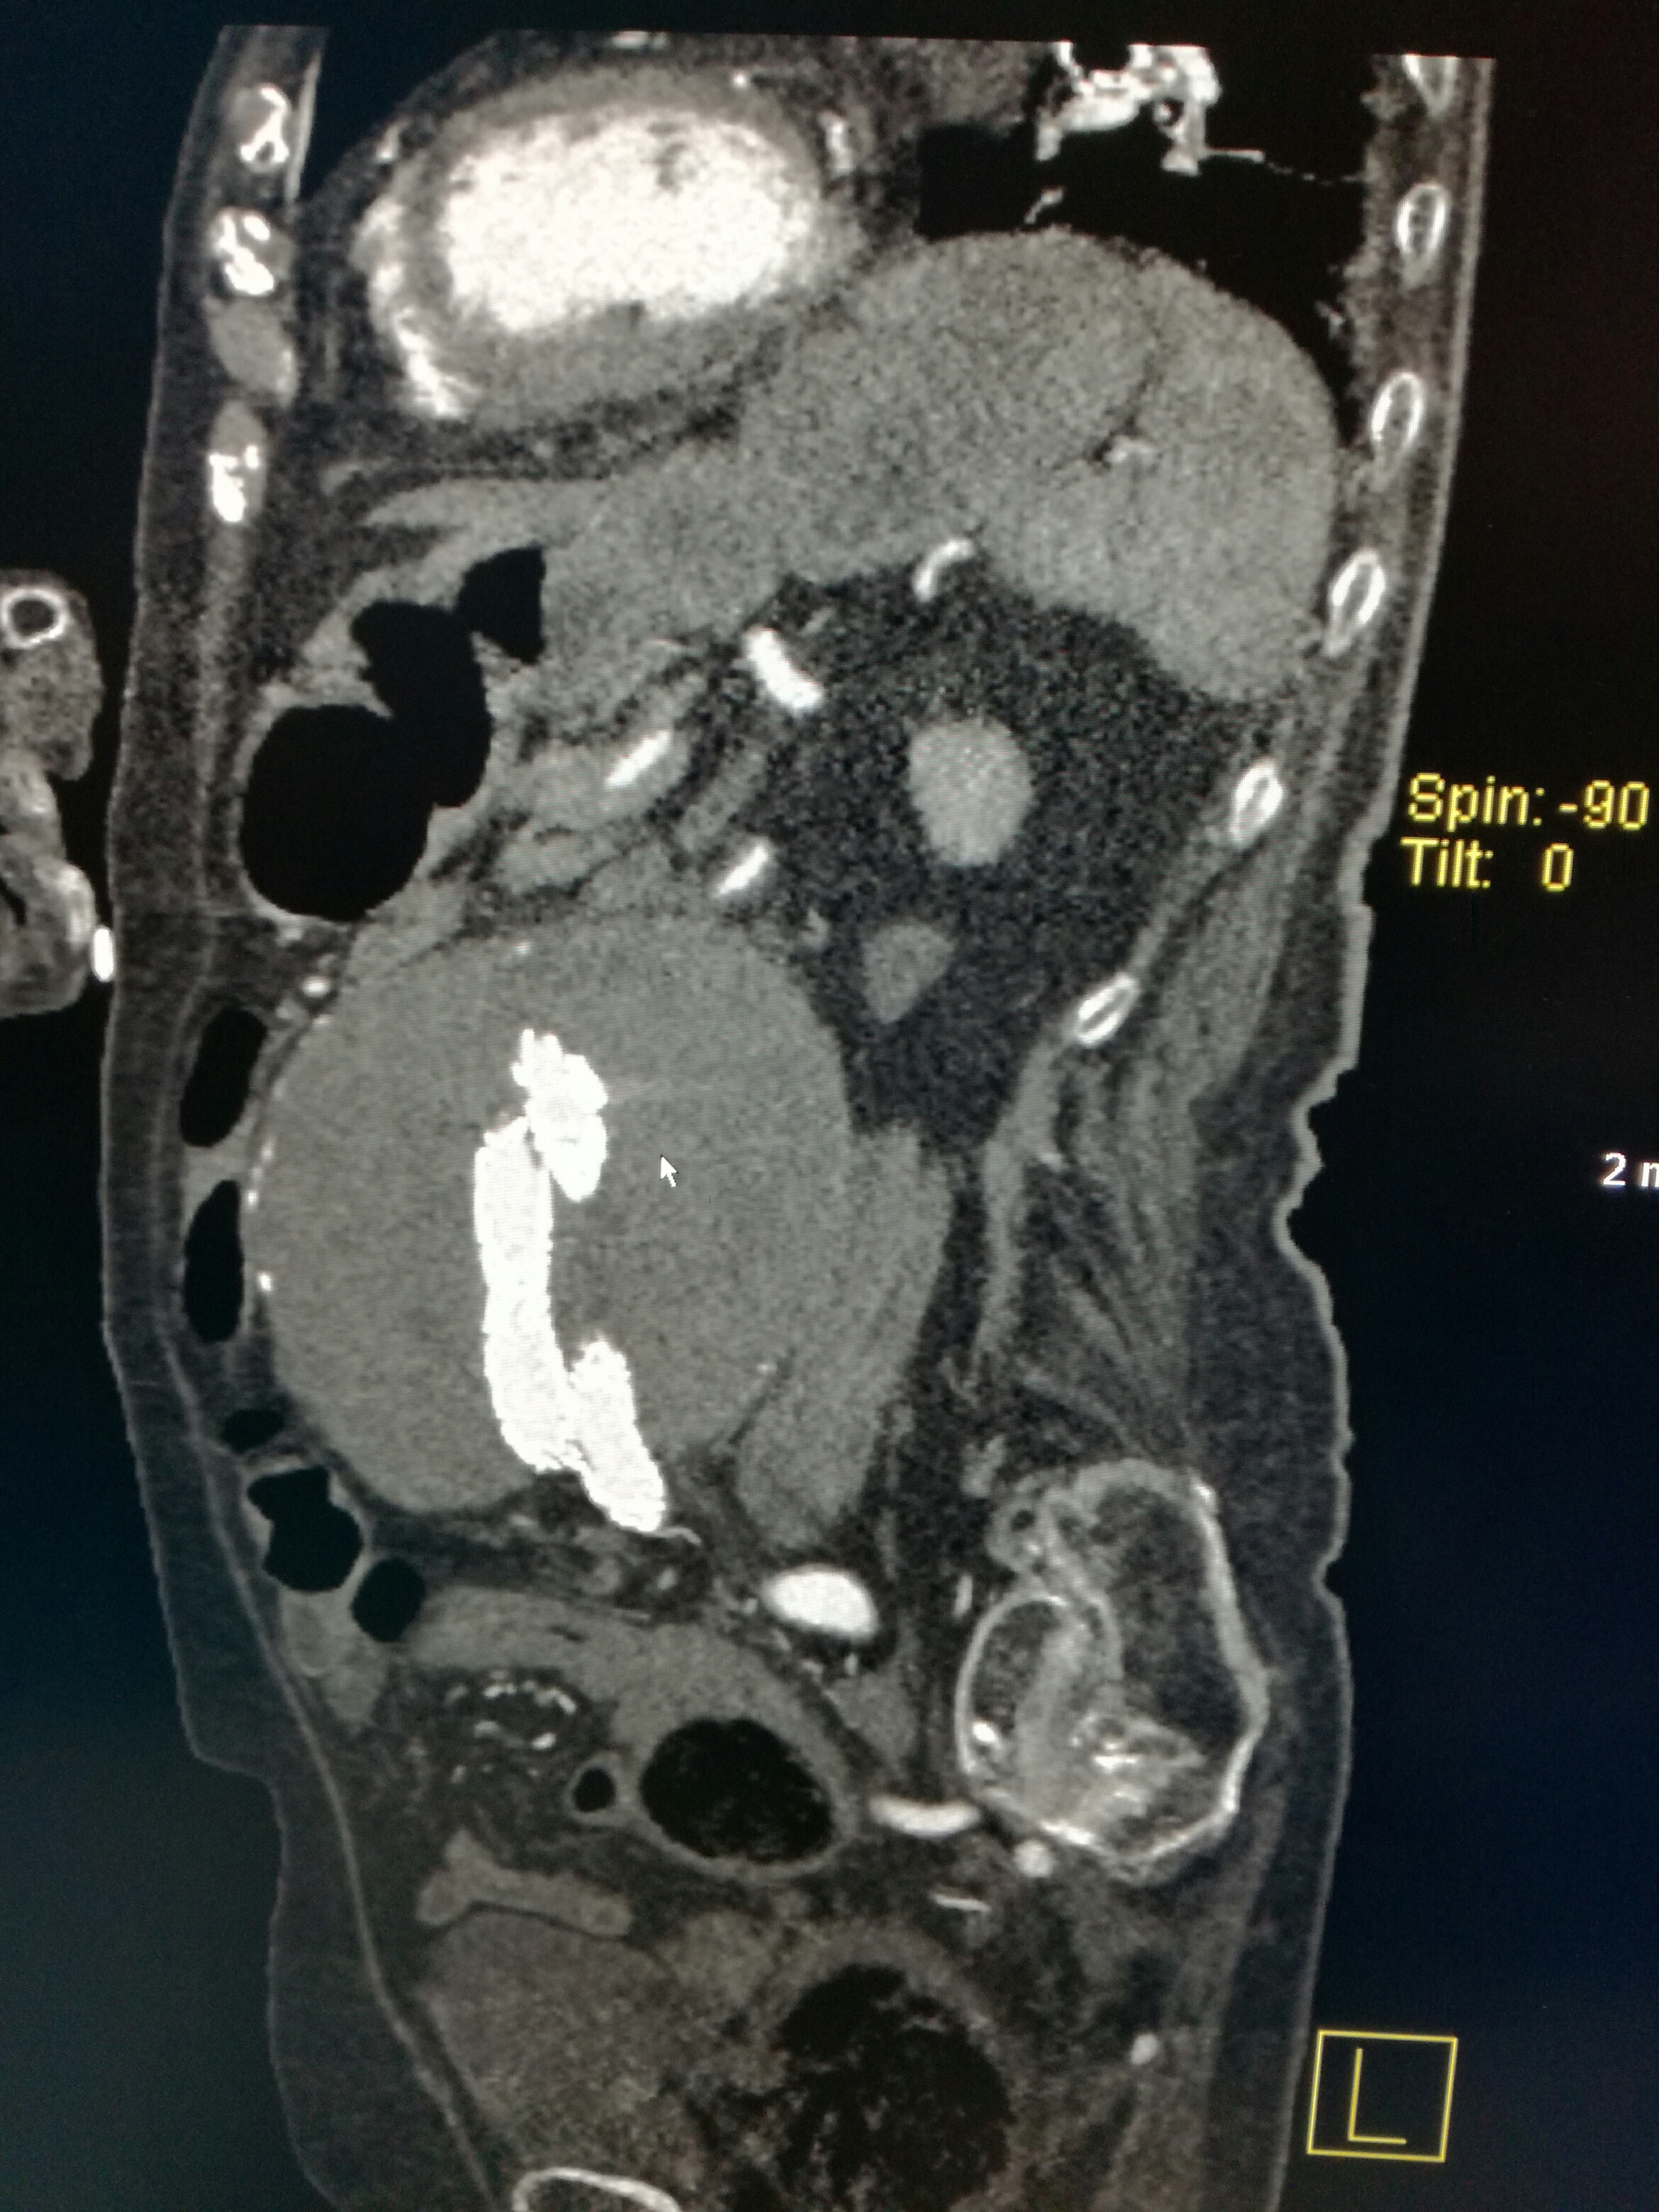

Ecco qua sotto le immagini impressionanti di ciò che troviamo in TC.

Cioè: “Presenza di sacca aneurismatica con diametro massimo trasverso di 15 cm con componenti iperdense all’interno già in fase diretta; dopo contrasto si osserva endoleak periprotesico distale di tipo III in corrispondenza della protesi iliaca destra; concomita aspetto ipertrofico di arteria lombare che sembra portarsi nella sacca aneurismatica sospetto per endoleak periprotesico di tipo II. Pervietà delle protesi e degli assi vascolari a monte e a valle della stessa.